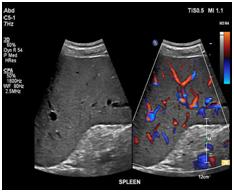

Your doctor has ordered an ultrasound of your abdomen. Ultrasound is a safe and painless procedure that uses sound waves to assess the structure of your internal body organs. The scan can help diagnose such medical conditions as abdominal masses, gallbladder disease and gallstones, as well as problems in the liver, kidneys, pancreas or spleen.

- Sound waves will bounce off certain organs and tissue in your body. This creates "echoes." The echoes are reflected back to the transducer, which converts them to electronic signals. A computer then processes the signals into pictures for radiologist evaluation.